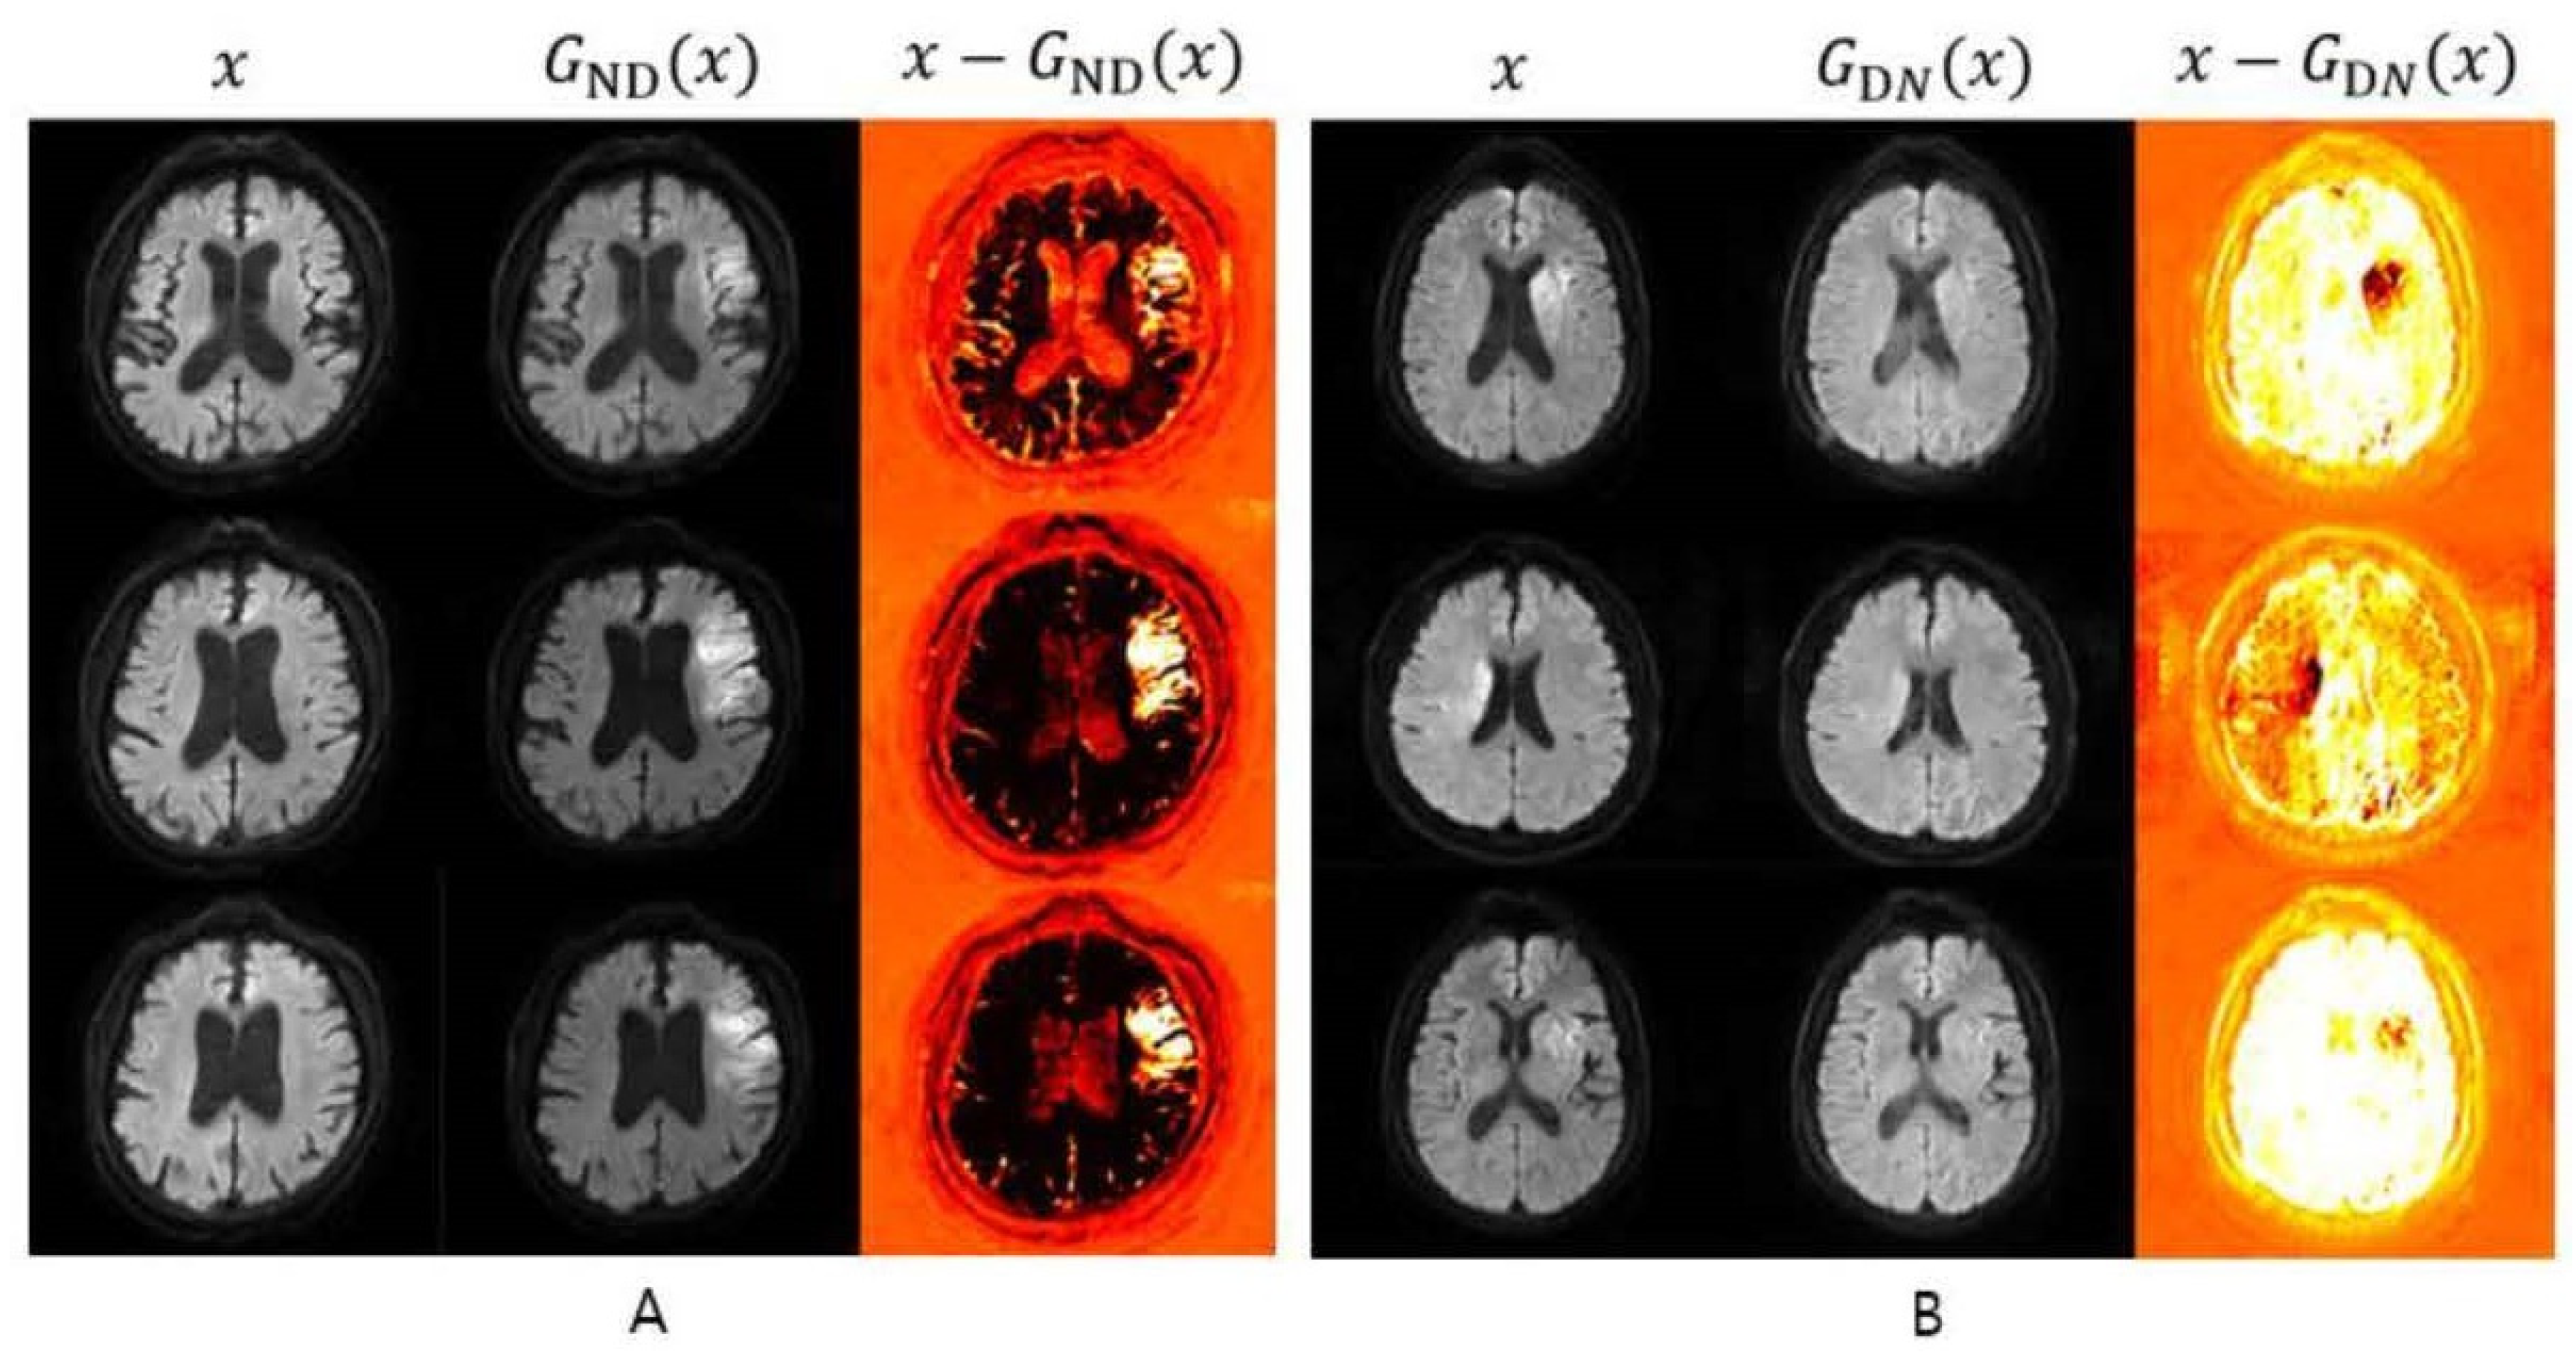

3.1.3. Unsupervised Detection Models

3.2.2. pSp Encoder-Combined StyleGAN—Brain Vessel Images for Unsupervised Anomaly Detection